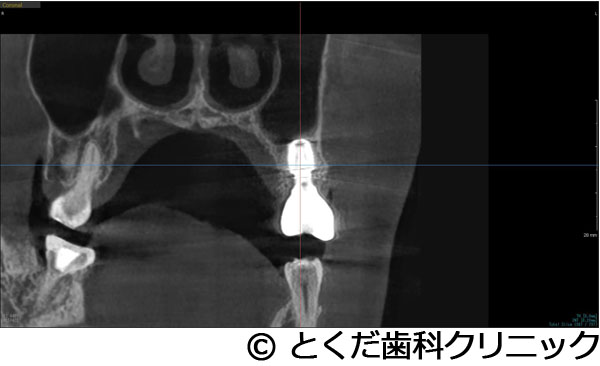

Åö¥¯¥ê¥Ë¥Ã¥¯¤Ç¤Ï¡¢¥ª¥Ã¥»¥ª¥Ç¥ó¥·¥Õ¥£¥±¡¼¥·¥ç¥ó½Ñ¤È¤¤¤¦¡¢¹ü¤ò°µ½Ì³ÈÂ礷³Ü¹ü¤Ë¥¤¥ó¥×¥é¥ó¥È¤òËäÆþ¤¹¤ë½Ñ¼°¤òºÎÍѤ·¤Æ¤¤¤Þ¤¹¡£

¥µ¥¤¥Ê¥¹¥ê¥¹¥È¡¦¥½¥±¥Ã¥È¥ê¥Õ¥È¤È¤¤¤Ã¤¿Áý¹ü¼ê½Ñ¤òȼ¤¦¾ì¹ç¡¢¾å³Üƶ¤Þ¤Ç¤Î¹üÎ̤¬1¡Á2ÐÄøÅ٤Ǥ⥤¥ó¥×¥é¥ó¥È¼£ÎŤ¬²Äǽ¤È¤Ê¤ê¤Þ¤¹¡£

»ÈÍѤ¹¤ë¥¤¥ó¥×¥é¥ó¥È¤â½¾Íè¤Îʪ¤ËÈæ¤Ùû¤¤Êª¤ä¡¢Ã»¤¯ÂÀ¤µ¤¬¤¢¤ë¥¤¥ó¥×¥é¥ó¥È¤ò»ÈÍѤ·¤Æ¤¤¤Þ¤¹¡£¤Þ¤¿¡¢¾å³Üƶ¤Ë¤Ï´µ¼ÔÍͼ«¿È¤Î¹ü¤òÆþ¤ì¤ë¤¿¤á¡¢´¶À÷¾É¤òÍÞ¤¨¡¢¼£ÎÅ´ü´Ö¤â2.5¡Á5¥õ·îÄøÅÙ¤ËÍÞ¤¨¤ë¤³¤È¤¬´üÂԤǤ¤Þ¤¹¡£

»õ¼þɤˤè¤ê¡¢±¦Â¦6È֤ξå³Ü¹ü¤¬µÛ¼ý¤·¤Æ¡¢1.5¡Á2mmÄøÅ٤ιü¤·¤«»Ä¤Ã¤Æ¤¤¤Ê¤«¤Ã¤¿¤¿¤á¡¢½¾Íè¤Ê¤éÂ礤ʿ¯½±¤È1ǯ°Ê¾å¤Î¼£ÎÅ´ü´Ö¤¬¤«¤«¤ë¥µ¥¤¥Ê¥¹¥ê¥Õ¥È¤¬É¬ÍפǤ¢¤Ã¤¿¤¬¡¢´µ¼ÔÍͤؤλþ´ÖŪ¡¢ÆùÂÎŪ¡¢¶âÁ¬ÅªÉéô¤¬Â礤¯¤Ê¤ë¤³¤È¤ò¹Íθ¤·¤Æ¡¢º£²ó¤Ï¡¢¥¨¥¯¥¹¥È¥é¥ï¥¤¥É¥·¥ç¡¼¥È¥¤¥ó¥×¥é¥ó¥È¤È¥Ç¥ó¥µ¡¼¥Ð¡¼¤ò»ÈÍѤ·¤¿¥°¥é¥Õ¥È¥ì¥¹¥µ¥¤¥Ê¥¹¥ê¥Õ¥È¤òÁªÂò¤·¤Æ¡¢¤ï¤º¤«¡¢2.5¥õ·î¤Ç¾åÉô¥¸¥ë¥³¥Ë¥¢¤ÎºÇ½ªÊäÄÖʪ¤òÁõÃ夷¤Æ¼£ÎŤò½ª¤¨¤Æ¤¤¤Þ¤¹¡£

¹âÅ٤˵ۼý¤·¤¿¾å³Ü¹ü¤ËÂФ¹¤ë¥¤¥ó¥×¥é¥ó¥È¼£ÎŤǤ¢¤Ã¤¿¤¬¡¢¥°¥é¥Õ¥È¥ì¥¹¥µ¥¤¥Ê¥¹¥ê¥Õ¥È¤ò¹Ô¤¦¤³¤È¤Ç¡¢Ã»»þ´Ö¡Ê11½µ¡Ë¤Ç¼£ÎŤò½ª¤¨¤ë¤³¤È¤¬¤Ç¤¡¢¾å³ÜƶÆâ¤Ë°Ûʪ¤Ç¤¢¤ë¿Í¹©¹ü¤ò»ÈÍѤ·¤Æ¤¤¤Ê¤¤¤¿¤á¤Ë¡¢¥µ¥¤¥Ê¥¹¥ê¥Õ¥È¤Ç¤è¤¯µ¯¤¤ë¹çÊ»¾É¤Î¾å³Üƶ±ê¤òÈò¤±¤ë¤³¤È¤¬¤Ç¤¡¢Ã»»þ´Ö¡¢Ä㿯½±¡¢Ä㥳¥¹¥È¤Ç¼£ÎŤò½ª¤¨¤ë¤³¤È¤¬¤Ç¤¤¿¡£¾å³Ü±¦Â¦6È֤˥¤¥ó¥×¥é¥ó¥È¼£ÎŤǤ¤¿¤³¤È¤Ë¤è¤ê¡¢Òû¹ç¤¬°ÂÄê¡¢»õ¼þɤˤ괵¤·¤Æ¤¤¤ë»õ¤Ø¤ÎÉ԰¤òÍÞ¤¨¤ë¤³¤È¤¬¤Ç¤¤¿¡£

´µ¼ÔÍͤ¬º¸¾å5¤ÎÇÓÇ¿¤ò¼çÁʤËÍ象¡¢¾Ã±ê¸å¤ËÈ´»õ¤ò´õ˾¤·¤¿¤¿¤áÈ´»õ¤ò¹Ô¤¤¤Þ¤·¤¿¡£¤½¤Î¸å¡¢´µ¼ÔÍͤ¬¥¤¥ó¥×¥é¥ó¥È¼£ÎŤò´õ˾¤·¤¿¤¿¤áÈ´»õ¸å¡¢¼þ°ÏÁÈ¿¥¤¬°ÂÄꤹ¤ë¤Î¤òÂԤäƥ¤¥ó¥×¥é¥ó¥È¼ê½Ñ¤ò¹Ô¤Ã¤Æ¤¤¤Þ¤¹¡£ÆâÍÆ¤Ï¡¢¾å³Ü´û¸¹ü¤¬Çö¤¤¤¿¤á¥°¥é¥Õ¥È¥ì¥¹¥µ¥¤¥Ê¥¹¥ê¥Õ¥È¤ÈʹԤ·¤Æ¡¢¹ü¤¬ÂçÉý¤Ë·ç»¤·¤¿Éôʬ¤Ø¤Î¹üÊäŶºÞŶÆþ¤ò¹Ô¤¤1²óË¡¤Ç¼ê½Ñ¤ò´°Î»¤·¡¢9½µ¸å¤Ë¸÷³Ø°õ¾Ý¤Ç°õ¾Ý¤ò¹Ô¤¤¡¢¥¸¥ë¥³¥Ë¥¢¤ÎºÇ½ªÊäÄÖʪ¤ò11½µ¤ÇÁõÃ夷¤Æ¼£ÎŤò´°Î»¤·¤Æ¤¤¤Þ¤¹¡£

ÂçÉý¤Ê¹ü·ç»¤¬¤¢¤Ã¤¿¤¬¡¢¥°¥é¥Õ¥È¥ì¥¹¥µ¥¤¥Ê¥¹¥ê¥Õ¥È¤È¹ü·ç»Éô¤Ë¿Í¹©¹ü¤òÊäŶ¤·¤Æ¡¢¤ï¤º¤«2¥õ·îȾ¤Ç¼£ÎŤò´°Î»¤¹¤ë¤³¤È¤¬¤Ç¤¤¿¡Ê²¾¤Ë¡¢GBR¤äÄ̾ï¤Î¥µ¥¤¥Ê¥¹¥ê¥Õ¥È¤ò¹Ô¤¤¼£ÎŤò¹Ô¤Ã¤Æ¤¤¤¿¤é¡¢ºÇÄã¤Ç¤â1ǯ¤Ï¤«¤«¤ë¥±¡¼¥¹¤Ç¤¹¡Ë¡£Ä㿯½±¤Ç¡¢Ã»»þ´Ö¤Ç¡¢¼£ÎŤò½ª¤¨¤ë¤³¤È¤¬¤Ç¤¡¢¤Þ¤¿¡¢¿³ÈþÀ¡¦µ¡Ç½À¤Î²óÉü¤â¹Ô¤¦¤³¤È¤¬¤Ç¤¤¿¡£

´µ¼ÔÍͤϺ¸¾å¤ÎưÍɤ¬º¸¾å56¤ÎÈ´»õ¤ò´õ˾¡£¤½¤Î¸å¡¢¥¤¥ó¥×¥é¥ó¥È¼£ÎŤò´õ˾¤·¤¿¤¿¤áº¸¾å4¤Ë´Ø¤·¤Æ¤ÏÈ´»õ¨»þËäÆþ¡£º¸¾å6¤Ë´Ø¤·¤Æ¤Ï¡¢´û¸¹ü1¡Á2mm¤Ç¥¤¥ó¥×¥é¥ó¥È¼£ÎŤ¬¸·¤·¤¤¾õÂ֤Ǥ¢¤Ã¤¿¤¬¡¢¥°¥é¥Õ¥È¥ì¥¹¥µ¥¤¥Ê¥¹¥ê¥Õ¥È¤Ç¥¤¥ó¥×¥é¥ó¥ÈËäÆþ¤ò¹Ô¤¤¤Þ¤·¤¿¡£¤½¤Î¸å¡¢2¥õ·îȾ¸å¡¢ÂçÉý¤Ë¹ü¤¬·ç»¤·¤Æ¤¤¤ë²¼³Ü56¤ËÂФ·¤Æ¥·¥ç¡¼¥È¥¤¥ó¥×¥é¥ó¥È¤ò»ÈÍѤ·¤Æ¡¢²¼³Ü¿À·Ð¤Î»½ý¤òÈò¤±¤Æ¥¤¥ó¥×¥é¥ó¥ÈËäÆþ¤Î¼ê½Ñ¤ò½ª¤¨¤Æ¤¤¤Þ¤¹¡£¤½¤Î¸å2¥õ·î¸å¤Ë¸÷³Ø°õ¾Ý¤Ç°õ¾Ý¤ò¹Ô¤¤¡¢º¸¾å456¤Ï3¥æ¥Ë¥Ã¥È¤Î¥¸¥ë¥³¥Ë¥¢¥Ö¥ê¥Ã¥¸¤òÁõÃå¡£²¼º¸56¤Ë´Ø¤·¤Æ¤Ï¹ü·ç»¤¬Â礤¤¤¿¤á¡¢»õ´§Ä¹¤¬¤À¤¤¤ÖŤ¯¤Ê¤ë¤¿¤á¡¢¥¸¥ë¥³¥Ë¥¢¤ÎÏ¢·ë´§¤òÁõÃ夷¤Æ¼£ÎŤò½ª¤¨¤Æ¤¤¤Þ¤¹¡£

¾å³Ü6¤Ë´Ø¤·¤Æ¤Ï´û¸¹ü¤¬¾¯¤Ê¤¯¡¢¸·¤·¤¤¼£ÎŤǤϤ¢¤ê¤Þ¤·¤¿¤¬¡¢5¥õ·î¤Ç¼£ÎŤò½ª¤¨¡¢´µ¼ÔÍͤοÈÂÎŪ¡¢»þ´ÖŪ¡¢ÈñÍÑŪÉéô¤òºÇ¾®¸Â¤ËÍÞ¤¨¤ë¤³¤È¤¬¤Ç¤¤¿¤È¹Í¤¨¤Þ¤¹¡ÊÄ̾ï¤À¤È¼£ÎŤ¬ÉÔ²Äǽ¤È¸À¤ï¤ì¤ë¤³¤È¤¬Â¿¤¤¥±¡¼¥¹¤À¤È¹Í¤¨¤Þ¤¹¡£¤Ç¤¤¿¾ì¹ç¤â¡¢½¾Íè¤Î¥µ¥¤¥Ê¥¹¥ê¥Õ¥È¤ò¹Ô¤¤¡¢1ǯ°Ê¾å¤«1Ç¯ÄøÅ٤μ£ÎÅ´ü´Ö¤¬¤«¤«¤ë¤«¡¢»þ´ÖŪ¤ä¿ÈÂÎŪ¤Ë¤â¡¢¤Þ¤¿¡¢ÈñÍÑÌ̤ˤª¤¤¤Æ¤â¡¢´µ¼ÔÍͤËÉéô¤ò¤«¤±¤ë¥±¡¼¥¹¤À¤È¹Í¤¨¤Þ¤¹¡Ë¡£¤Þ¤¿¡¢²¼³Ü¤Ï¹ü·ç»¤¬Â礤¯¡¢²¼»õÁå´É¤Ø¤Î±Æ¶Á¤¬¹Í¤¨¤é¤ì¤ë¥ê¥¹¥¯¤¬¹Í¤¨¤é¤ì¤ë¥±¡¼¥¹¤Ç¤·¤¿¤¬¡¢¥·¥ç¡¼¥È¥¤¥ó¥×¥é¥ó¥È¤ò»ÈÍѤ¹¤ë¤³¤È¤Ç°ÂÁ´¤Ë¼£ÎŤò½ª¤¨¤ë¤³¤È¤¬¤Ç¤¤Þ¤·¤¿¡£